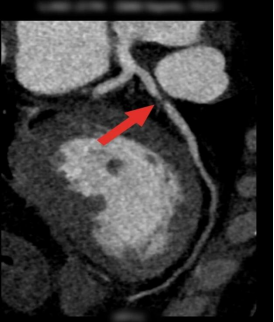

● 冠脉CTA(冠状动脉CT血管造影):该项检查可以判断血管的狭窄程度或者堵塞。

心导管术:该项检查可以显示出心脏中的任何动脉是否堵塞。